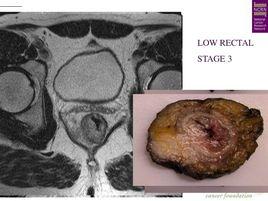

(三)CT、MRI、腔內B超: